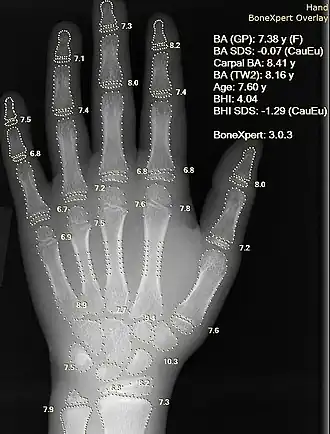

Information can take the form of images, sound, video or other multimedia. Bits of information can be streamed via signals. Its processing is the central notion of informatics, the European view on computing, which studies information processing algorithms independently of the type of information carrier – whether it is electrical, mechanical or biological. This field plays important role in information theory, telecommunications, information engineering and has applications in medical image computing and speech synthesis, among others. What is the lower bound on the complexity of fast Fourier transform algorithms? is one of the unsolved problems in theoretical computer science.

FFT algorithms Image processing Speech recognition Data compression Medical image computing Speech synthesis